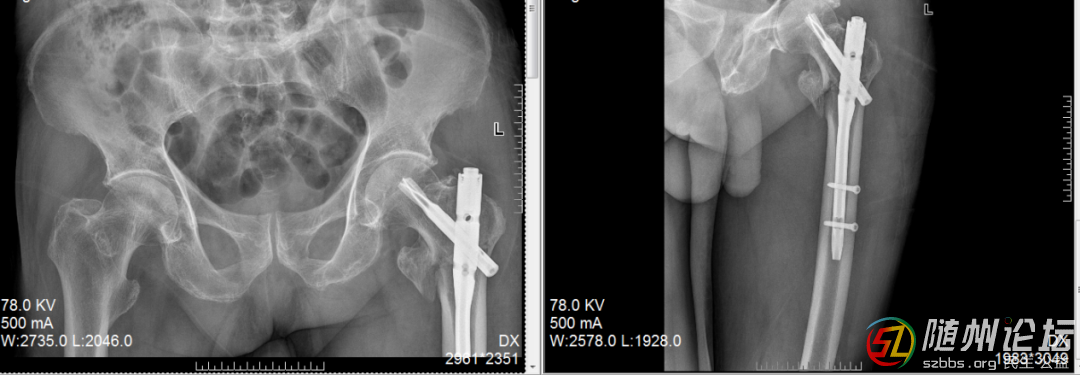

高齡老人髖部骨折,降低臥床風險

一位高齡老人摔傷導(dǎo)致髖部骨折,我們采用了微創(chuàng)的“鑰匙孔”式微創(chuàng)內(nèi)固定術(shù)。手術(shù)時間短、出血少,老人第二天就可以在床上坐起、活動腿腳,一周內(nèi)嘗試站立,大大降低了長期臥床的風險。